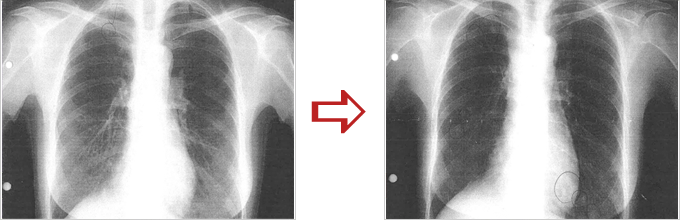

肺癌、腹膜転移

横内漢方治療前と後